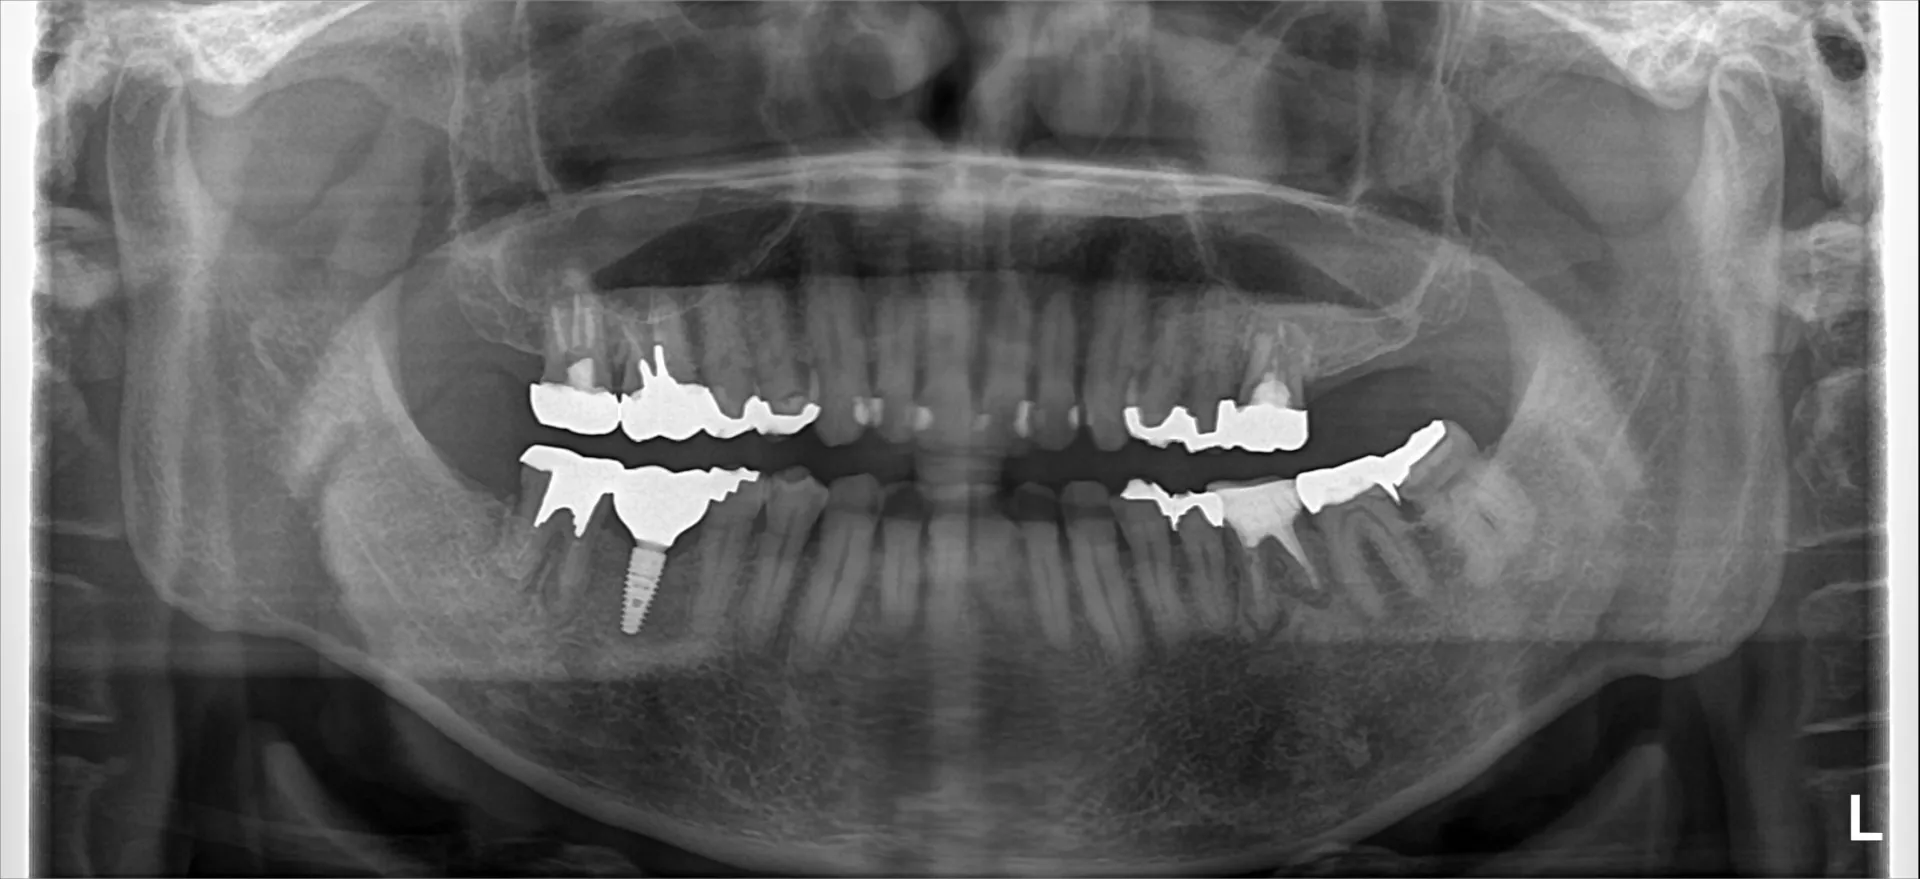

今回は抜歯になってしまった歯からインプラント治療完了までの流れについてご紹介いたします。